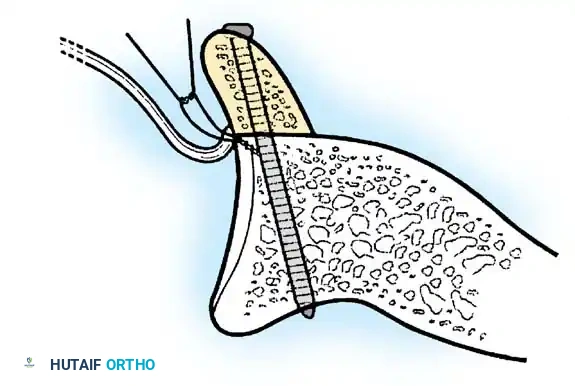

- Anchor Placement: Suture anchors (typically 3 to 4) are placed along the articular margin of the anteroinferior glenoid (from the 5:30 to 3:00 positions for a right shoulder). Anchors must be inserted at a 45-degree angle to the articular surface to maximize pullout strength and avoid joint penetration.

- The inferior capsular flap is advanced superiorly and laterally, tensioning the IGHL complex. The sutures from the anchors are passed through the shifted capsule and tied.

- The superior flap is then brought down over the inferior flap in a "pants-over-vest" fashion to reinforce the anterior wall and close the rotator interval.